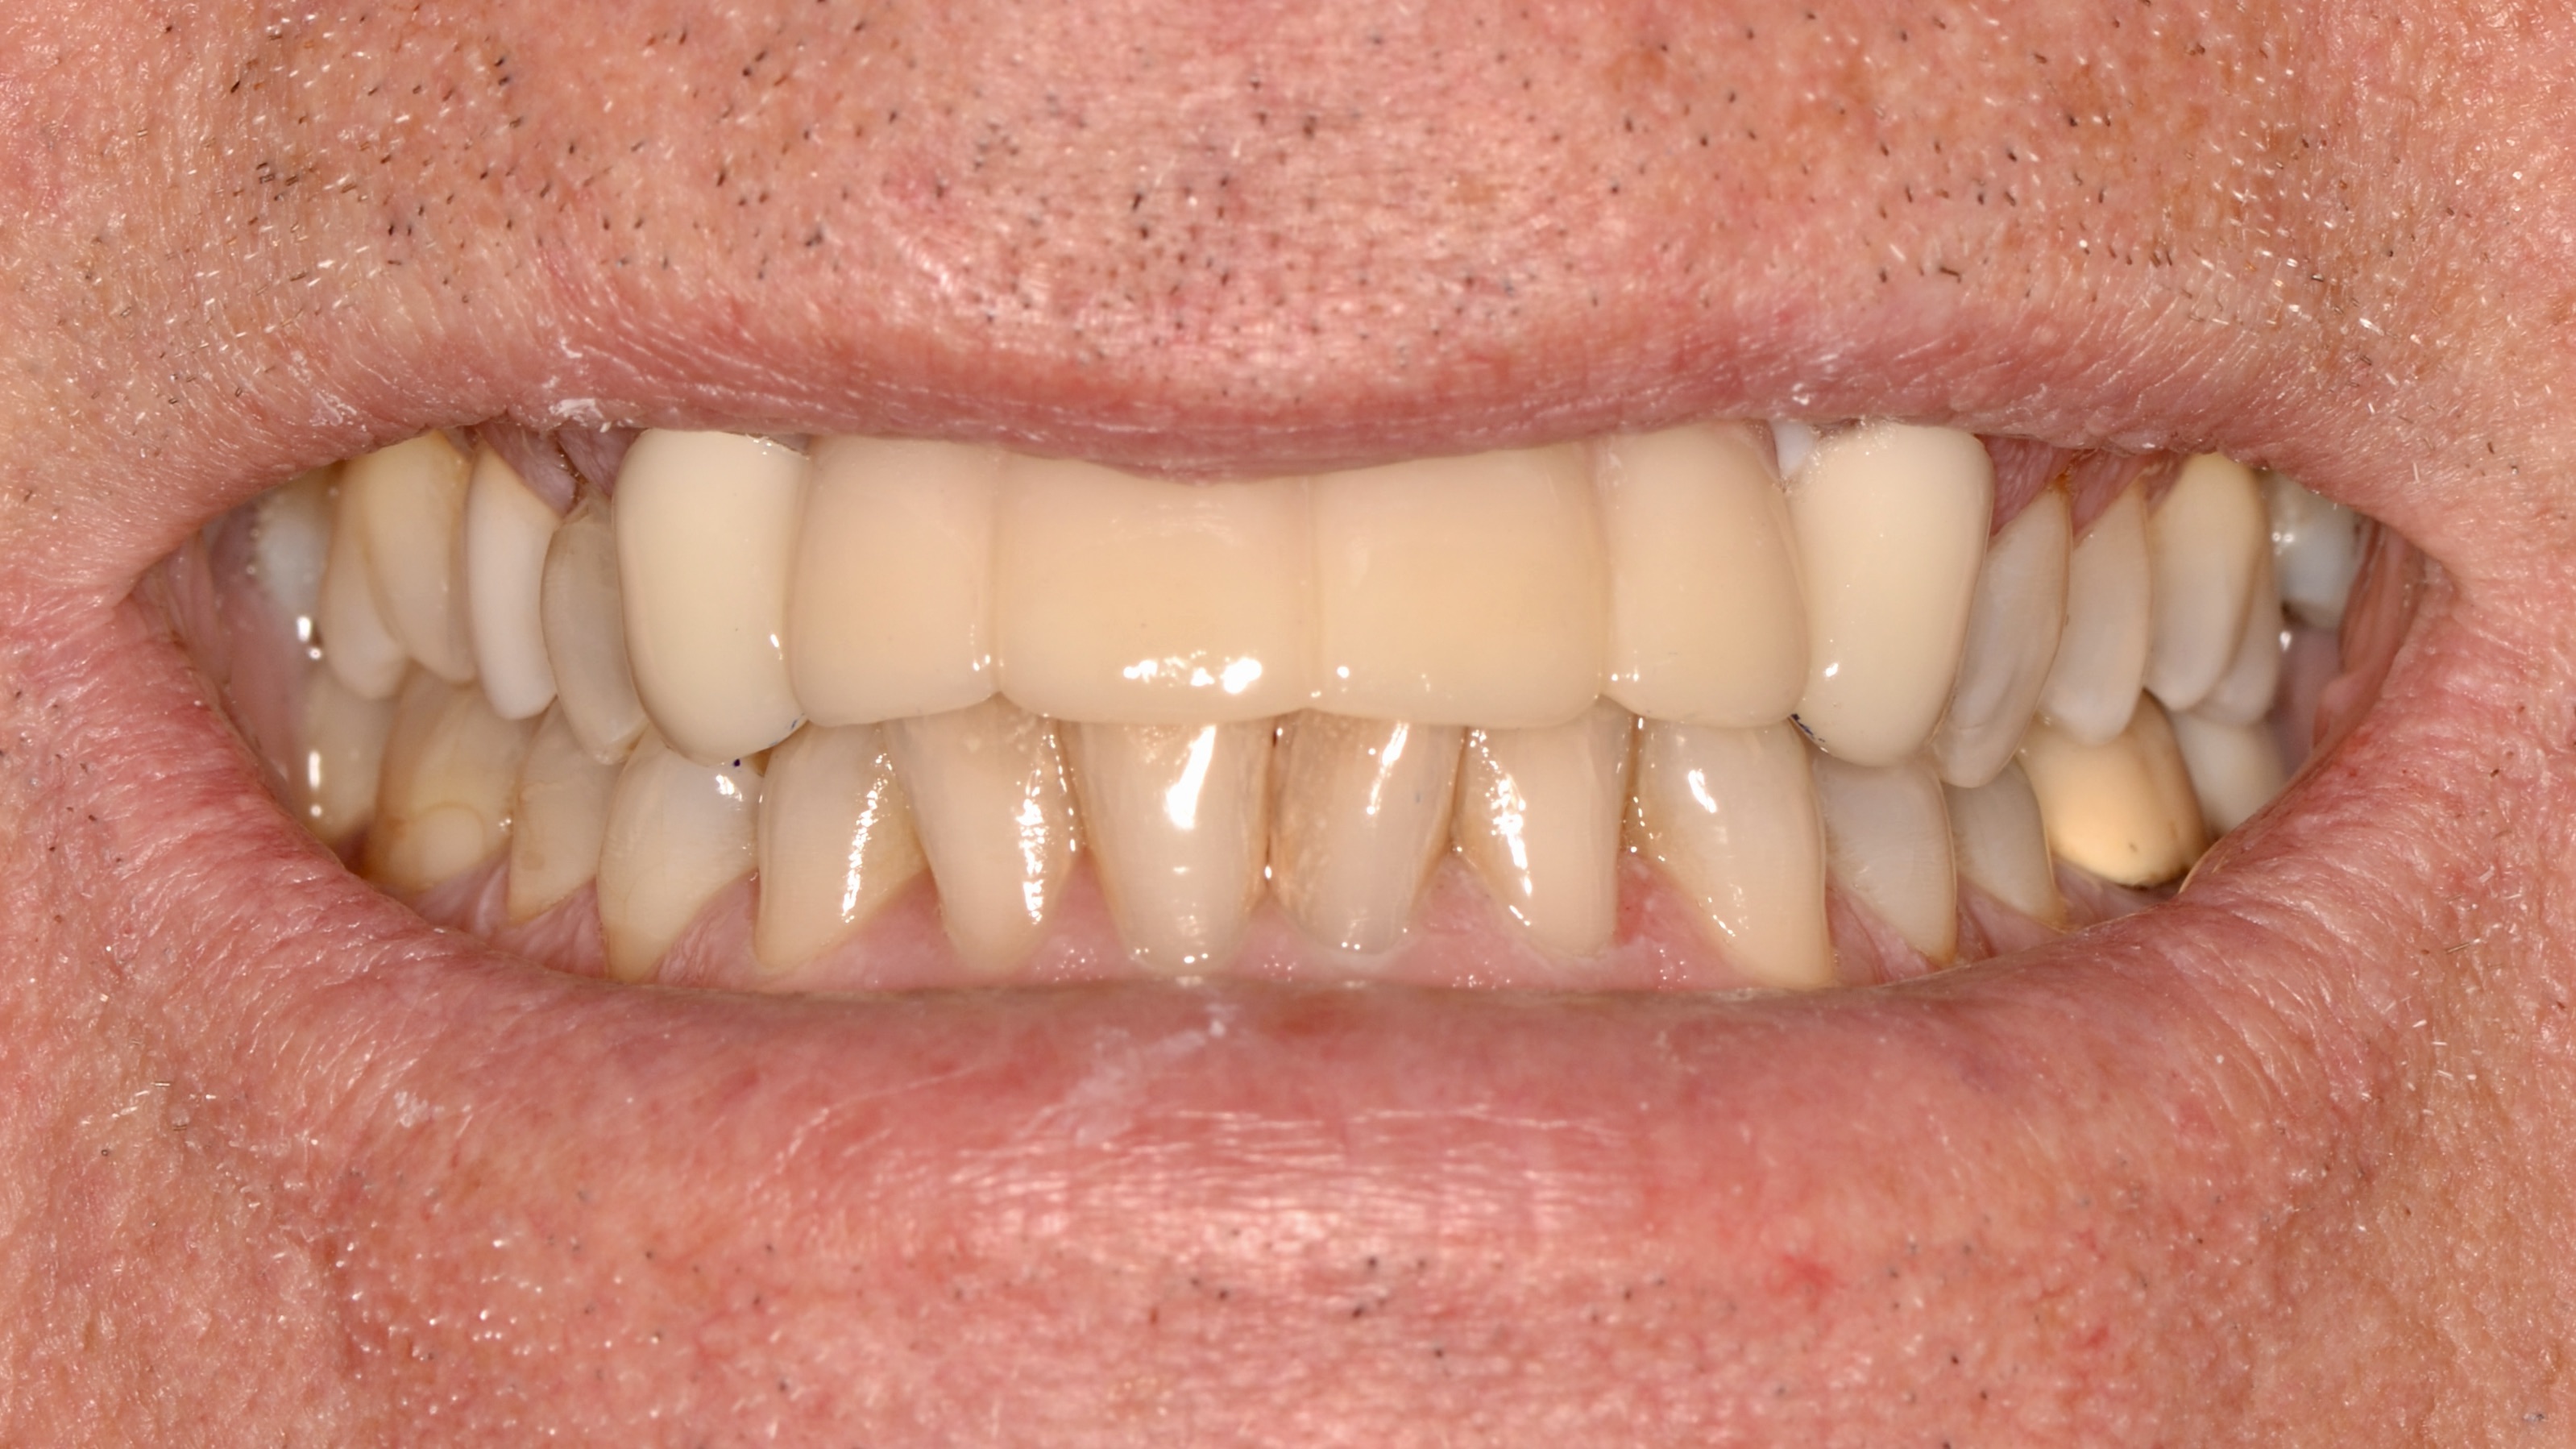

Custom Ceramic Crowns